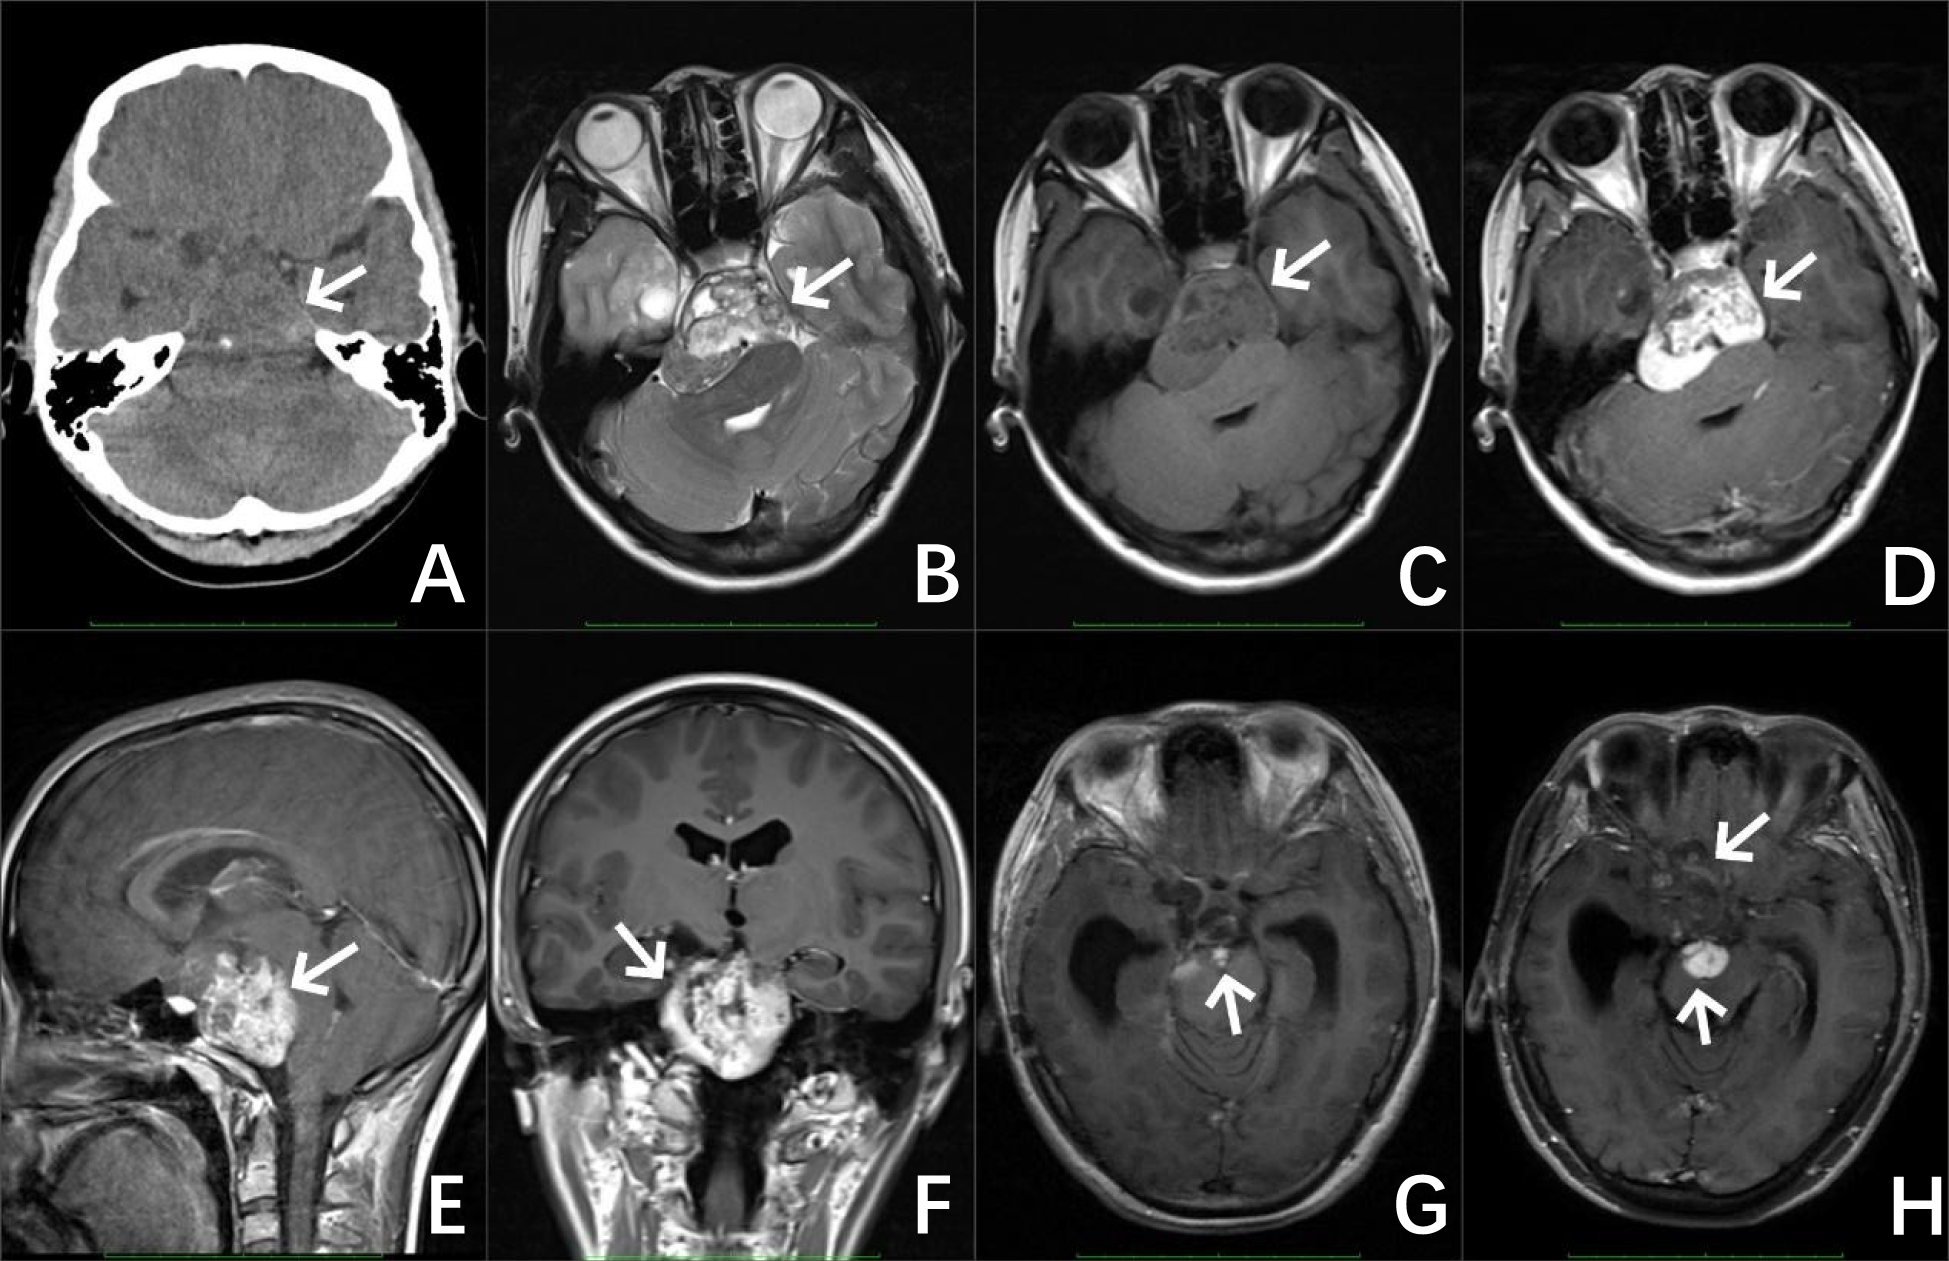

CT of the brain showed an oblong slightly low-density shadow with a clear boundary that could be seen in the saddle area, measuring 42 mm × 49 mm × 47 mm, with a speckled calcification. The adjacent brain stem was compressed and shifted backward, and the bone in the clivus region was compressed and thinned. Magnetic resonance imaging (MRI) of the brain revealed irregular mixed-signal mass shadows in the suprasellar cistern, ambient cistern, and interpeduncular cistern, measuring 62 mm × 53 mm × 50 mm, with relatively clear boundaries and uneven enhancement. The brain stem was compressed and deformed, the optic chiasm and bilateral cavernous sinuses were unclear, and the supratentorial ventricles were dilated (Figure 1). An immature cholesteatoma was diagnosed based on the image. Subsequently, she underwent a right temporal craniotomy with an anterior inferior temporal petrosal approach for resection of the majority of the slope lesions.

Figure 1. Preoperative image of the patient, CT of the brain (A) revealed an irregular jumble density mass with a well-defined boundary and a speckled calcification in the sellar region (as shown by the white arrow). MRI results of the brain (B–F) revealed irregular mixed signals and a markedly enhanced mass in the suprasellar cistern, ambient cistern, and interpeduncular cistern. Image of the patient after the operation (G) MRI of the brain revealed a few abnormal enhanced shadows at the operative area. Image of the patient 5 years after the operation (H) MRI of the brain revealed a significant increase in the area of abnormal enhancement at the surgical area.

An MRI of the brain 3 months later revealed some abnormal signals in the surgical area, which were considered tumor residue. An MRI of the brain 2 months after revealed that the amount of abnormal enhancement in the surgical area was approximately the same as before, and a follow-up review was continued. The patient returned to the doctor 5 years later with frequent headaches, and a re-examination showed that the residual extent of the operative area was significantly larger than before and involved the right frontal and temporal lobes, considering the progression of the residual part of the tumor.